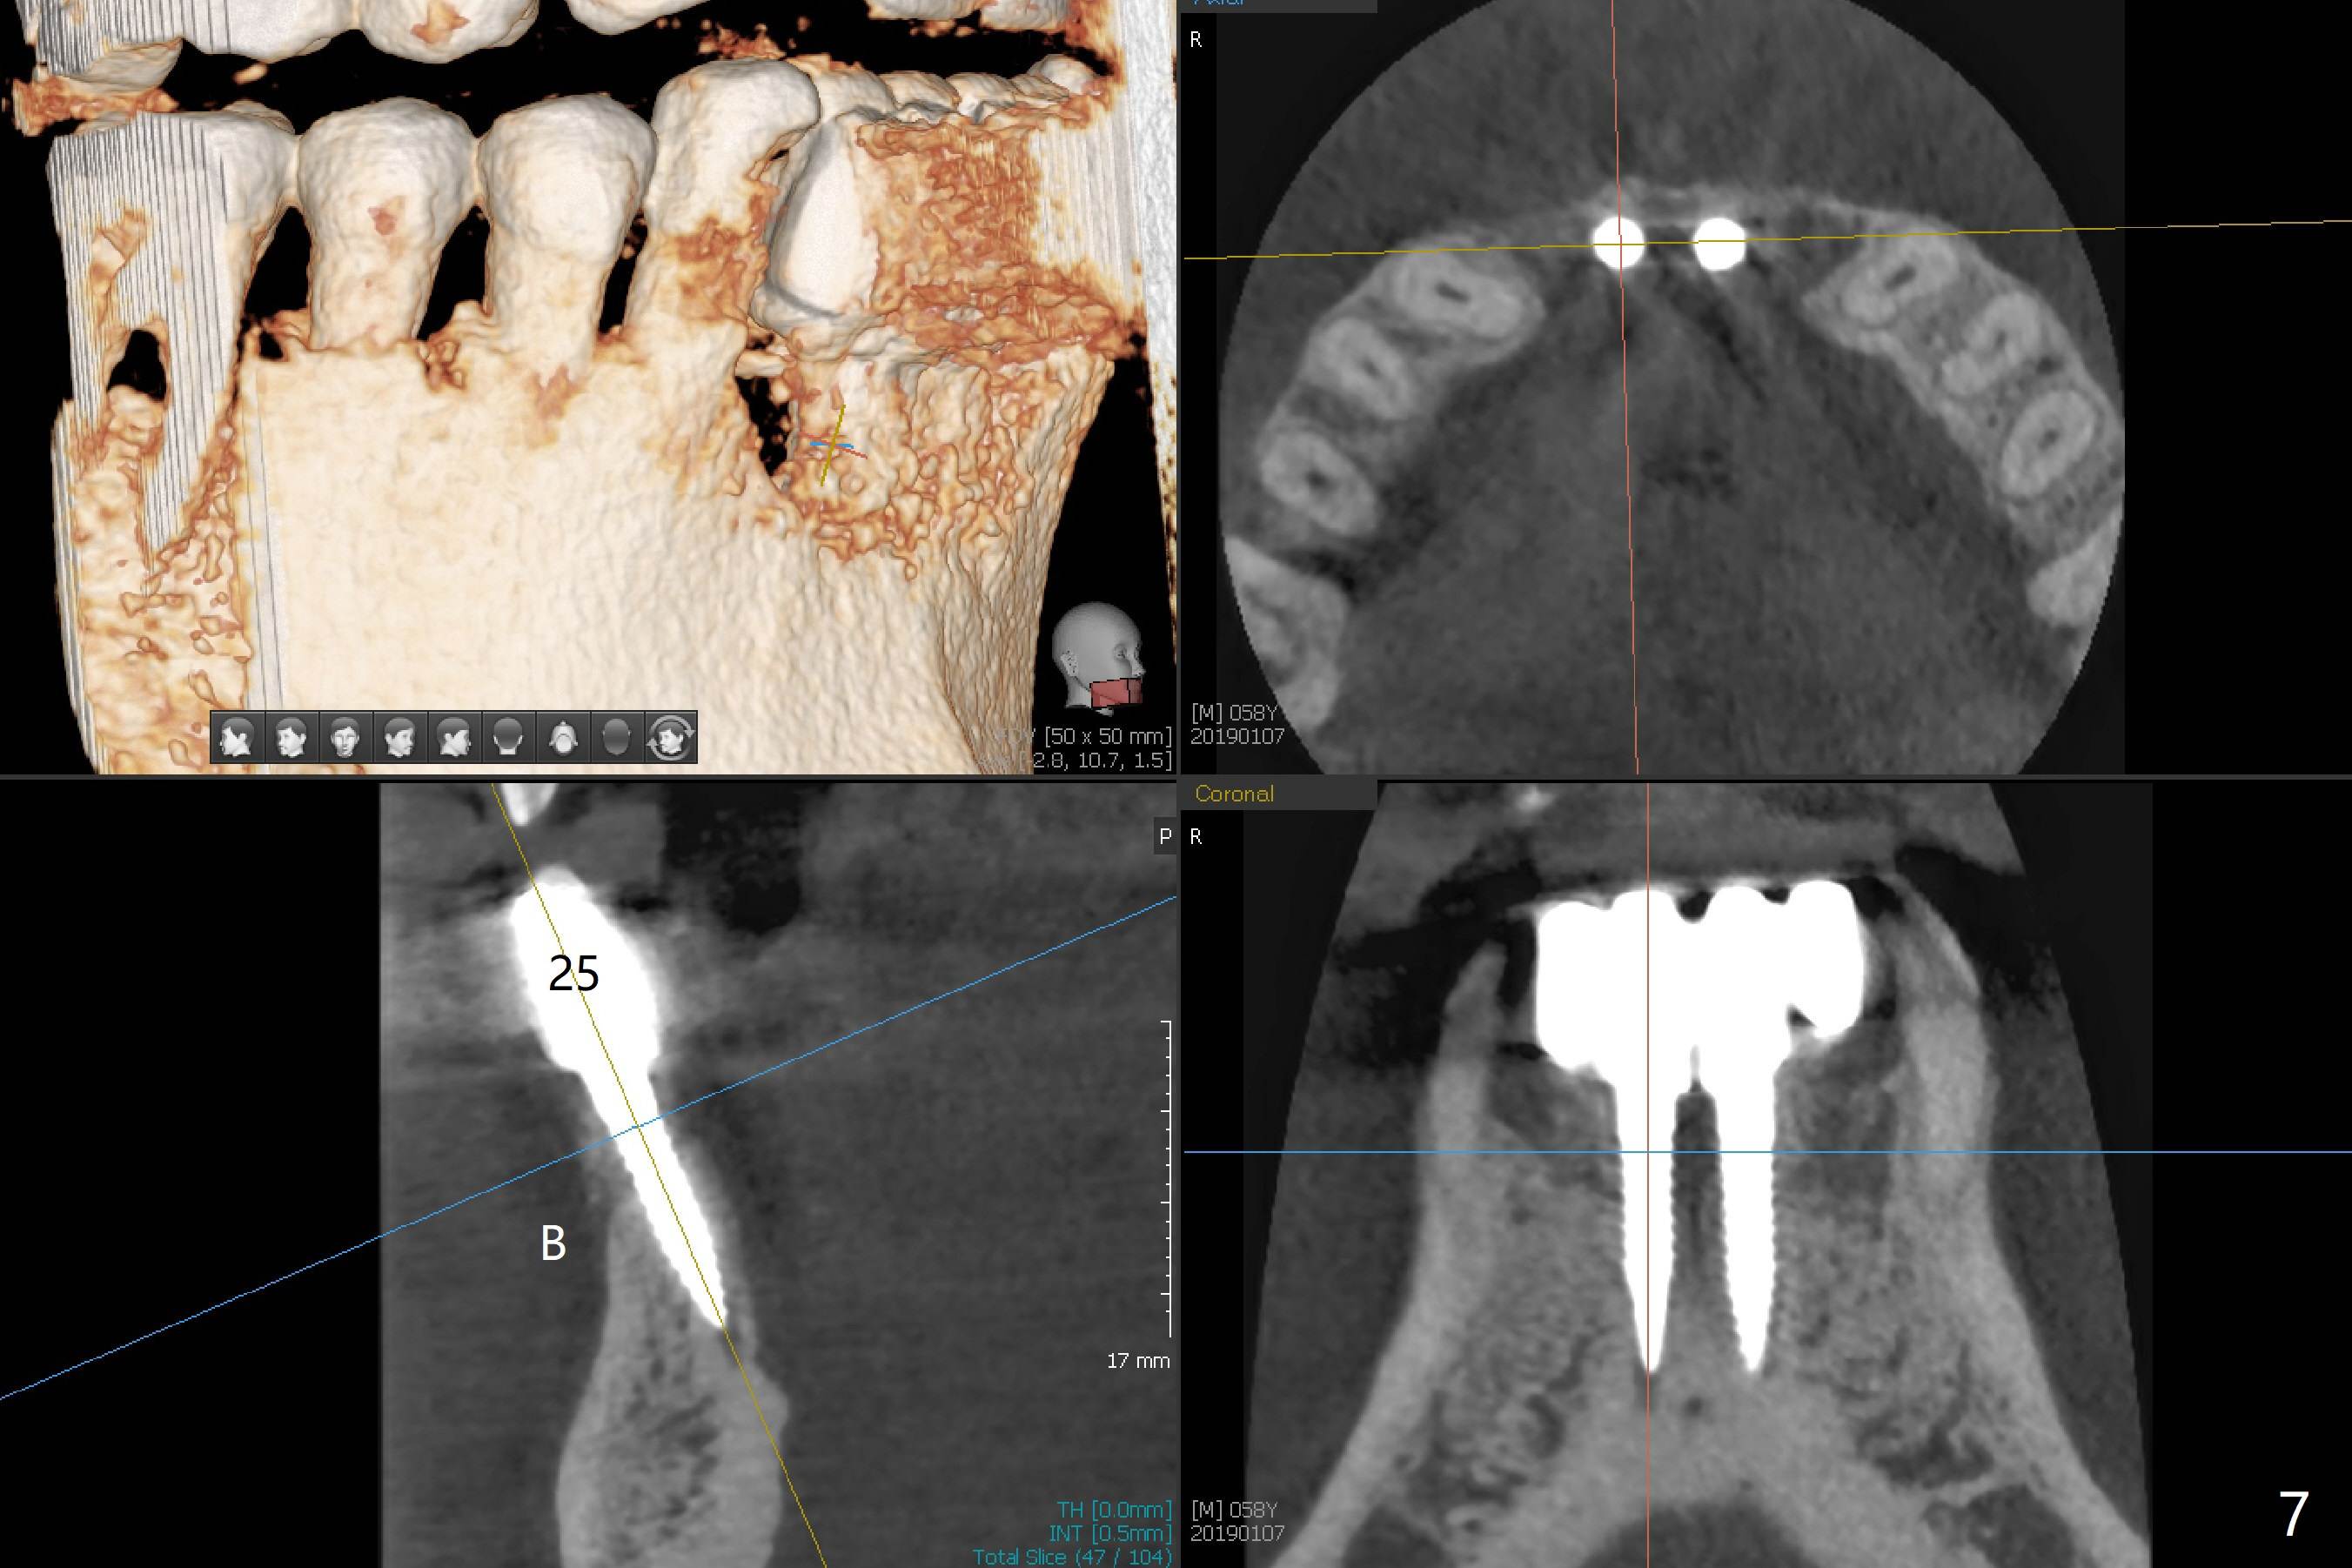

The fenetration found buccal to #25 two months post cementation persists, although asymptomatic, 4 months post cementation. Blood is drawn for PRF. In fact the implants at #24 and 25 are exposed buccal; there is limited amount of the buccal bone (Fig.1 *). After granulation tissue removal, Titanium brush is used to clean the implant threads. Allograft and Osteogen are mixed with PRF liquid to form gel, which is placed over the exposed implant threads. The bone graft is covered with a piece of PRF membrane and a piece of collagen membrane (Fig.2 C). Immediately postop PA (Fig.3) and CBCT (Fig.4) show that the implants have sufficient clearance between them. The implant thread exposure is most likely due to failure to place the implants deep enough and the implants are slightly large relative to the ridge (Fig.5-8). If the bone graft does not heal, new type of 1-piece implants (Fig.9,10 (green) smaller in diameter, 2 or 2.5 mm ) with longer abutment (pink) will be placed subcrestal buccal with guide.